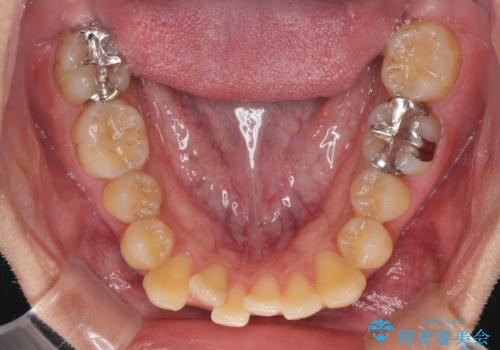

前歯のクロスバイトをインビザラインで矯正治療

- 前歯のデコボコとクロスバイトを気にして来院された患者様です。

前歯を早く整えたいとの希望があったので、ワイヤー矯正にて短期間でクロスバイトを解消し、その後インビザラインにて整えることとしました。

インビザラインによる前歯のクロスバイト改善におけるリスクとして、前歯歯髄充血・歯髄壊死が挙げられます。

ワイヤー矯正を併用する目的として、短期間でデコボコやクロスバイトを改善する他に、歯髄充血リスクを低減させるというものがあります。